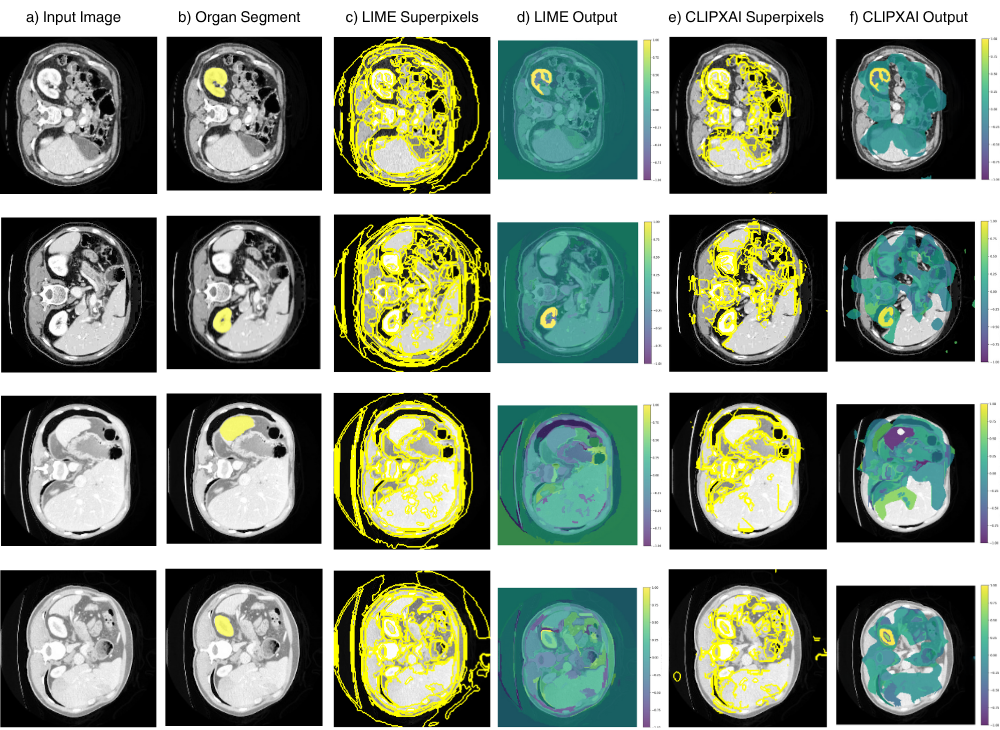

LIME generates explanations by locally approximating the behavior of a complex model with an interpretable surrogate model [3]. The approach partitions the input image into superpixels and constructs a set of perturbed samples by randomly enabling or disabling these regions [7]. The influence of each superpixel is then estimated by analyzing the corresponding changes in the model’s output, enabling identification of regions that most strongly affect the segmentation outcome. In our implementation, we evaluated multiple superpixel generation strategies, including QuickShift, SLIC, and Felzenszwalb, each of which yields distinct explanation heatmaps and emphasizes different spatial and structural characteristics of the segmentation process as shown in Fig 3.

In further experiments with LIME, we employ Felzenszwalb superpixel segmentation with parameters tailored to medical imaging characteristics. Specifically, the scale parameter is set to 100 to balance structural detail preservation with computational efficiency, sigma is fixed at 0.5 to apply mild Gaussian smoothing while maintaining organ boundary integrity, and min_size is set to 50 to prevent over-fragmentation of non-clinical features. Superpixel generation is constrained to predefined regions of interest by zeroing out pixels outside the ROI and assigning sequential labels to ROI superpixels. This restriction effectively reduces a image to approximately 150 semantically meaningful regions, enabling more focused and efficient perturbation analysis.

Similarly, as shown in Table 3, using occlusion sensitivity as the underlying perturbation strategy for XAI-CLIP resulted in the most pronounced performance gains among all evaluated methods. Quantitatively, this configuration achieved improvements of 44.6% in Dice coefficient and 96.7% in Intersection-over-Union relative to conventional occlusion-based explanations. These gains are further supported by qualitative assessment, which reveals substantially reduced noise, sharper boundary delineation, and improved spatial coherence in the generated saliency maps when compared to baseline approaches as demonstrated in Fig. 10.

This is worth noting that the LIME-based analysis exhibited notable performance variability, with Dice and IoU values spanning from below 0.1 to as high as 0.893 and 0.802, respectively. In contrast, the traditional LIME baseline frequently failed to localize the target organs altogether, yielding dice scores close to zero in numerous test cases as shown in Fig. 11, highlighting the limitations of unguided perturbation in complex anatomical settings.

Notably, XAI-CLIP-LIME successfully identified anatomical structures even in scenarios where the baseline method completely failed. In instances where both methods achieved reasonable localization, XAI-CLIP-LIME maintained significant heatmap quality, as shown in Fig 12, while simultaneously reducing computational requirements by in GFLOPs and approximately in runtime. However, the consistently poor baseline performance (below in many cases) precluded meaningful percentage improvement calculations for this method.